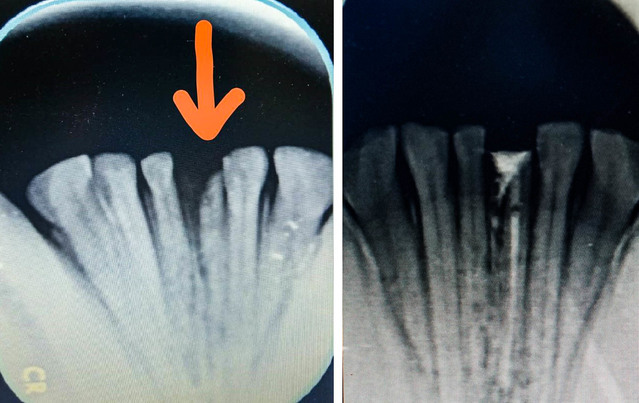

台北市立動物園今(23)日表示,保育員日前於例行訓練課程中發現大貓熊「圓仔」左下側門牙牙冠斷裂,導致牙髓暴露,園方立即與獸醫及醫療顧問團聯繫,討論如何日常護理及進行治療。對此,醫療團隊在19日為圓仔麻醉,以便為圓仔治療斷牙與健康檢查,因牙醫團隊考量拔牙後產生的空隙會影響鄰牙移位,所以選擇採用根管治療的方式,保留牙根,清理乾淨後封填起來,順利完成牙齒治療,未來將繼續觀察圓仔的牙齒狀況。

園方指出,這是圓仔自出生以來的第二次麻醉健康檢查,圓仔這次除了斷牙的處理外,也進行全身性的健康檢查,透過獸醫師團隊與「野生動物健康照護與醫療小組」臺大醫院麻醉部黃啟祥醫師、臺灣大學牙醫專業學院林俊彬教授、李正喆醫師所率領的醫師團隊分工合作下,圓仔的健康檢查順利於2小時內完成。